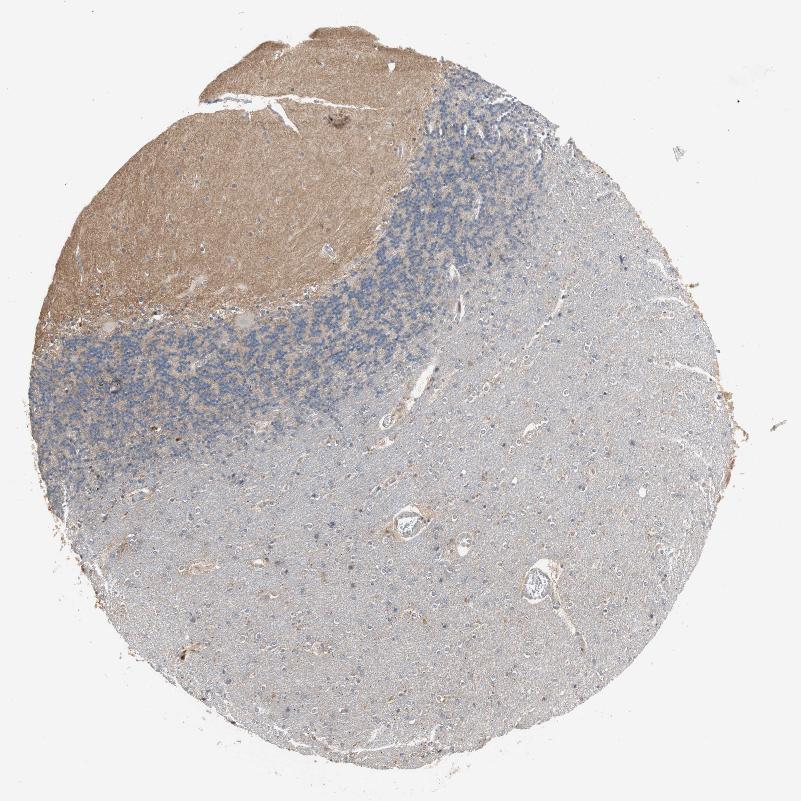

CEREBELLUM - Antibody stainingi

Antibody staining in the annotated cell types in the current human tissue is reported as not detected, low, medium, or high, based on conventional immunohistochemistry profiling in selected tissues. This score is based on the combination of the staining intensity and fraction of stained cells.

Each image is clickable and will lead to virtual microscopy that enables deeper exploration of all samples and also displays staining intensity scores, fraction scores and subcellular localization as well as patient and tissue information for each sample.

Antibody HPA005709

Purkinje cells Not detected

Cells in granular layer Low

Cells in molecular layer Not detected